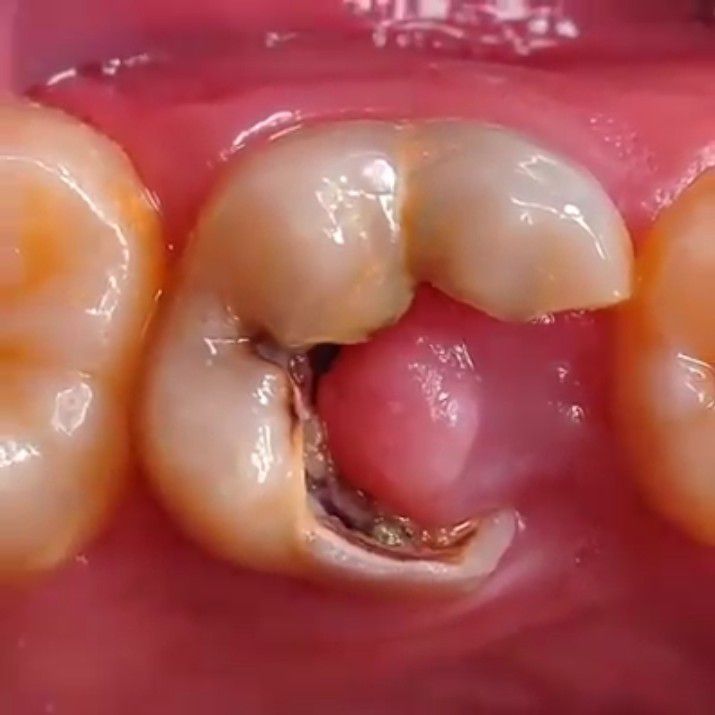

Pulp Polyp

Otherwise known Chronic Hyperplastic Pulpitis. The pulp polyp is the result of both mechanical irritation and bacterial invasion into the pulp of a tooth that exhibits significant crown destruction due to trauma or caries